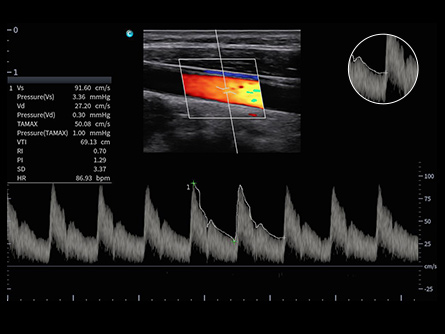

Potencie su práctica en Atención Primaria con las máquinas de ultrasonido de CHISON diseñadas para versatilidad y precisión. Nuestros productos están adaptados para abordar una amplia gama de necesidades de diagnóstico, ofreciendo interfaces fáciles de usar para exámenes eficientes. Las soluciones de ultrasonido de Atención Primaria de CHISON proporcionan imágenes claras y controles intuitivos, respaldando a los médicos generales en la realización de diagnósticos precisos y en la atención integral de los pacientes.